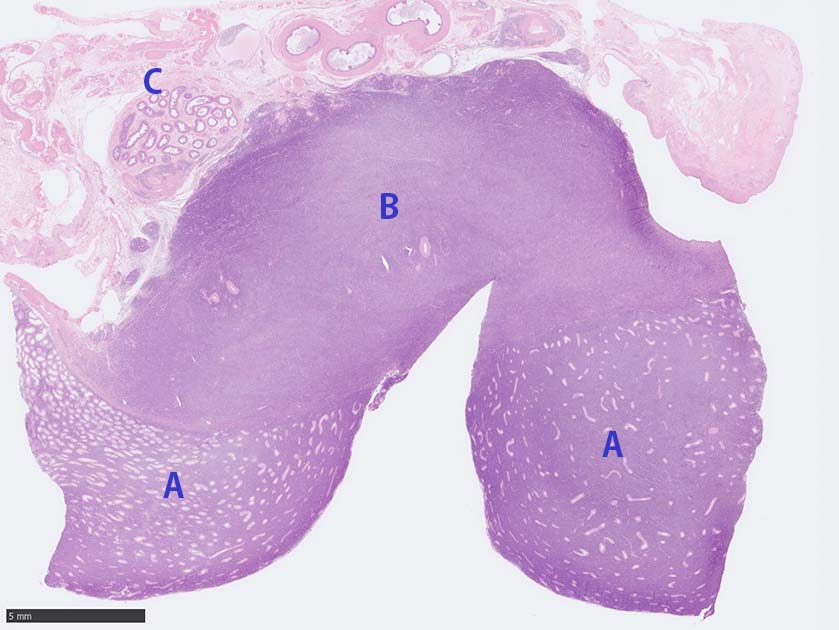

睾丸腫瘤マクロ, loupe像 (サムネイル像のクリックで大きな画像がみられます)

loupe像では, 腫瘍細胞が髄様密に浸潤増殖する部位と, 精細管をスペアするように管間に腫瘍細胞が浸潤する部分(右端図 A)がある.

切り出し図とは天地を逆にした右端図では, 髄様密な部分は白膜内で増殖するリンパ腫瘤(B)であることがわかる. 精巣上体の一部に浸潤がみられる(C)